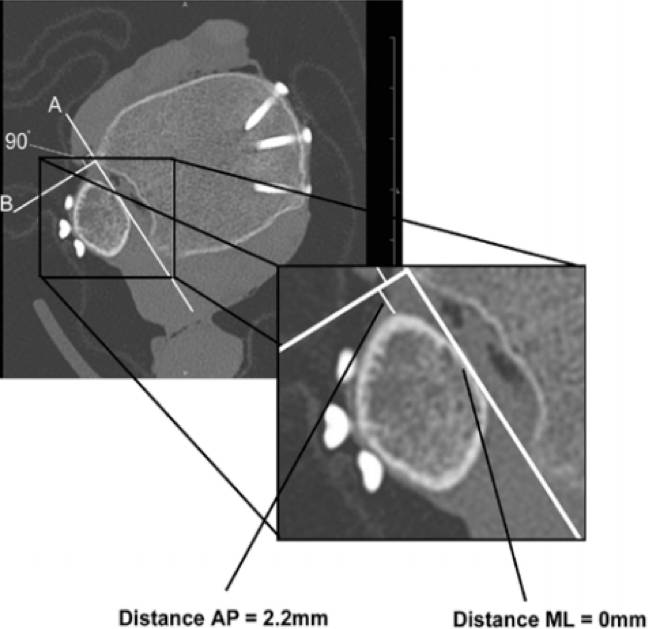

CT平扫片上建立坐标系(如图A、B线)

• 测量远端腓骨至B线最近距离(AP)

• 测量远端腓骨至A线最近距离(ML)

• 二维平面上综合反映远端腓骨移位情况

• 更为全面,研究中已逐步应用